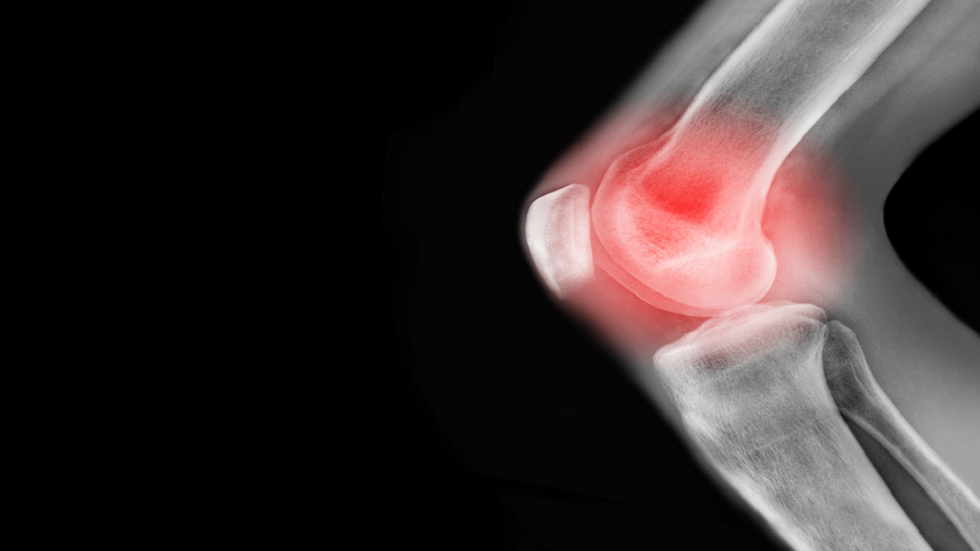

تناول هذا الطعام مرتين في الأسبوع لتخفيف ألم التهاب المفاصل

واقترحت أن إضافة هذه الأطعمة إلى نظامك الغذائي المتوازن قد يساعد في تخفيف الألم وأعراض التهاب المفاصل الأخرى.وقالت هيئة الصحة البريطانية NHS: “إذا كنت تعاني من زيادة الوزن، فإن فقدان الوزن يمكن أن يساعدك حقًا في التعامل مع التهاب المفاصل، حيث يضع الوزن الزائد ضغطًا زائدًا على مفاصل الوركين والركبتين والكاحلين والقدمين، مما يؤدي إلى زيادة الألم ومشاكل في الحركة”.

هشاشة العظام هي أكثر أنواع التهاب المفاصل شيوعًا في المملكة المتحدة، حيث تصيب حوالي ثمانية ملايين شخص، بينما يصيب التهاب المفاصل الروماتويدي أكثر من 400 ألف شخص.

يمكن أن تختلف أعراض التهاب المفاصل من أسبوع لآخر، لذلك قد يأتي ألم المفاصل ويختفي.وتتمثل الأهداف الرئيسية لعلاجات التهاب المفاصل في تقليل الأعراض وتحسين نوعية الحياة.